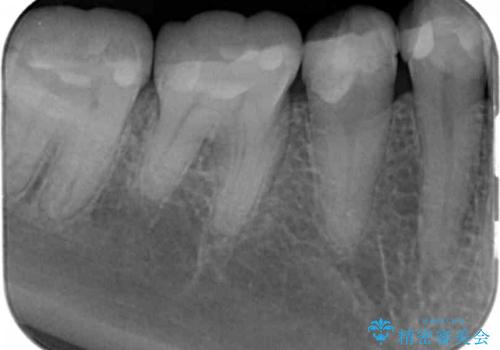

- 樹脂の材料の着色が気になるとのことで来院されました。

継ぎ接ぎになっている部分が多かったためクラウンでの治療となりました。

樹脂の材料と歯の境界部分は虫歯・着色の好発部位となります。

度重なる治療で継ぎ接ぎになってしまった場合はクラウンで歯を覆った方が虫歯・着色のリスクを減らすことができます。